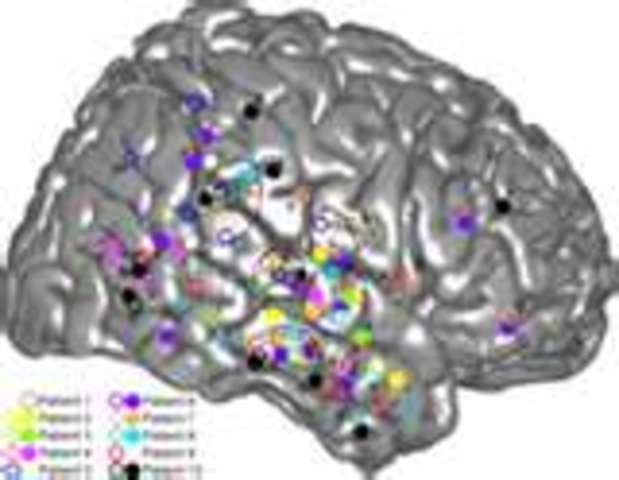

• Allison, McCarthy, & Colleagues Conduct Intracranial Research at Yale

Allison, McCarthy, & Colleagues Conduct Intracranial Research at Yale

In the 1990's Allison, McCarthy, & Colleagues from Yale University conducted intracranial research on over 100 patients. By placing electrodes in direct contact with the brain's cortical surface, the studies confirmed what was discovered earlier: signals appeared in the left hemisphere for words and the right hemisphere for faces. Furthermore, single electrodes would react massively to words while its neighboring electrodes exhibited no response. These were later termed microterritories.

• Allison et al Discover Left-hemisphere Preference for Words vs. Faces

Allison et al Discover Left-hemisphere Preference for Words vs. Faces

Neurologists Truett Allison, Gregory McCarthy, and colleagues at Yale University surgically placed electrodes in direct contact with the cortical surface, confirming the incredible speed of our visual system and verifying data from all other sources. "The ventral surface of ...brain contains a systematic arrangement of visual recognition devices, all tuned to different categories of images... the letterbox area is..sandwiched between areas responsive to faces and objects" (Dehaene 82).